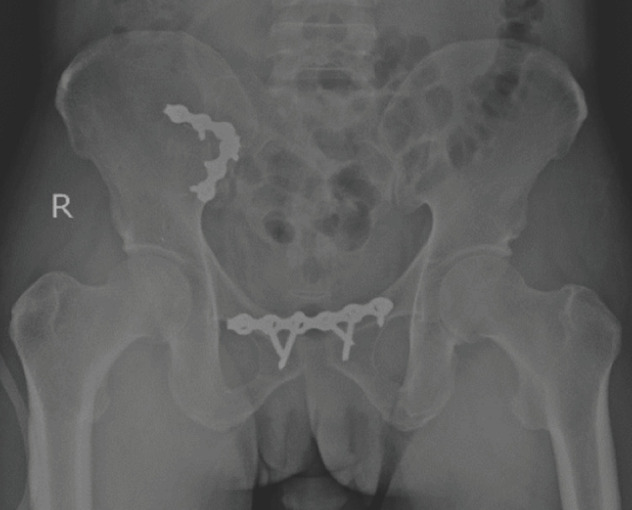

Material and methods: This retrospective study involved 15 patients with unstable pelvic injuries requiring surgical intervention from January 2015 to December 2020 who undergone anterior stabilisation of the sacroiliac joint. Radiological outcome assessments were done postoperatively by using Lindahl criteria. The complete functional outcome was assessed at least six months postoperatively when patients were able to weight bear by using Majeed system. Descriptive statistical analysis was performed using IBM SPSS Statistics Version 27.

Results: The participants consist of 73.3% male and 26.7% female patients. A total of 66.7% of patients had a Tile type B pelvic ring injury, and the remaining 33.3% had a Tile type C pelvic ring injury. Based on the Majeed system, 73.3% of patients had excellent functional outcomes, and based on Lindahl criteria; there were 60% of patients who had excellent radiological outcome. However, there was no significant agreement between functional and radiological outcomes.

Conclusion: Definitive fixation of the sacroiliac joint by anterior plate stabilisation provided an excellent functional and radiological outcome mainly due to good anatomical reduction and mechanical stability. However, further study may be needed to evaluate the correlation between functional and radiological outcomes and compare the various method of fixation with a larger sample size.